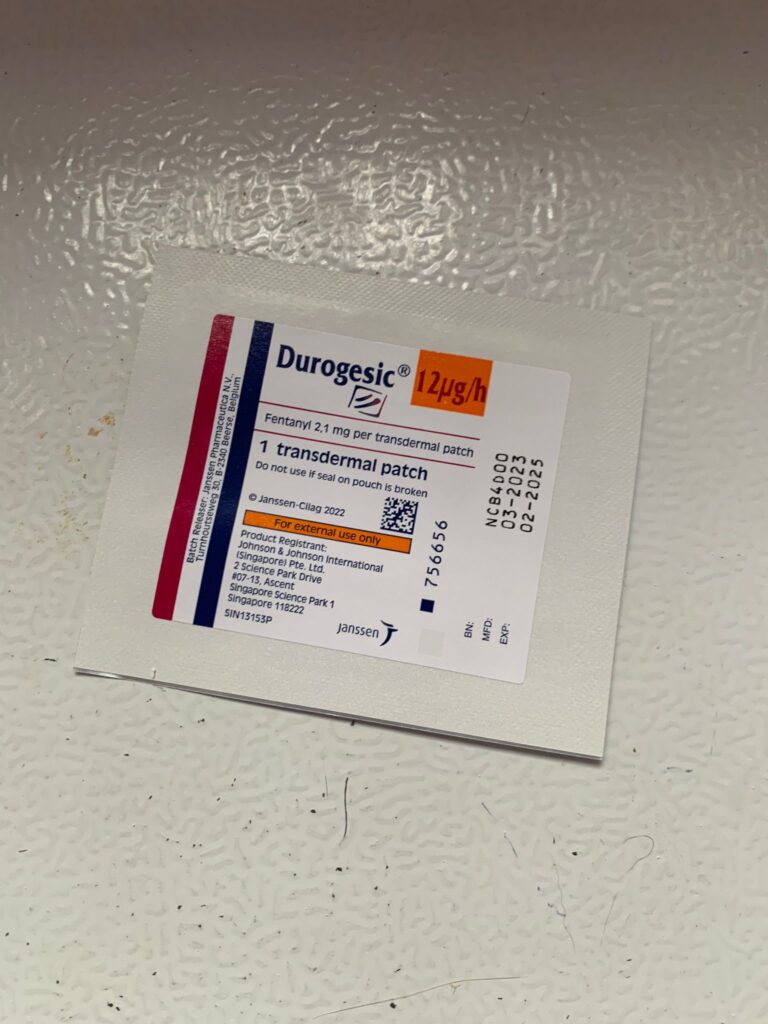

10am+: still look uncomfy despite f patch.

Night: Tmr got to put new f patch for him or give bupre alr

Morning; electric work today … they will stay in food room till Friday bah after cleaning then let them back. Looks pain again. Bupre given.

10am: eyes more discharge I assume is due to pain, today will shave his ear and put f patch and give bupre and Subcut

Night: his patch is still on but he still look uncomfortable

Night; did looks more in pain. Bupre in the day not enough. Have to put f patch

Morning: looks in pain. Give Subcut and bupre. I don’t have f patch in 5G. scanned on 19.4.24 no m/c.

Morning: got helper in to cut nails, steam bath and clean ears. She can handle him alone. Given Subcut bupre n put on f patch for him.

Morning: got 2 helpers in to clean up and for him: cut nails, clean ears and steam brush fur. His f patch if off, given Subcut and bupre jab

Morning; both eyes discharge look bad, clean up and put banocin on his ear. Will Subcut him and give Clav jab and bupre n put on new f patch for him

Morning: f patch intact. Apply banocin powder on ear. Still look got blood clog, didn’t bleed further. Given 5th and last Clav jab.

Morning: Subcut n on regular med and place new f patch n still given bupre

2pm+: did call out when I’m there. F patch intact. Didn’t even eat selar fish

Morning: just logging down that past days he isn’t on any painkiller cos bupre no more. Tmr morning will put on a f patch and give him bupre also

10am+: b4 I Subcut n give painkiller still eating ok. Subcut and given b12 b com bupre and put on a f patch (end 1.3.24)

Morning: looks in pain. F patch still on. Given Subcut n Buprenophine.

Morning: alr in more regular bupre but today looks much more in pain. Tmr I need to give him f patch also

11Am+: given bupre jab and place a f patch on his left ear.

Morning: didi constipated, saw him in 2 bins, trying to squeeze out something n can’t n he try to rub on floor – aren’t that pushing that piece in? I help him push out the 2cm piece 5/10, and he go to bin 03 and poo out another 12cm. So is that piece stuck n he is so uncomfortable. Subcut him w bupre also. His f patch still on. Can tear off soon. Need to buy more

Morning: will meow. Like to eat Sanyo pink elderly food. His f patch still on it

Just status update: Today Subcut n given b12 b com also. Given bupre and fercosang also. eye more discharge. Pain. Shave his ear and place a f patch also.

Morning: sometime he will meow n meow at me. Want me sayang? In pain? Want some snacks? I sayang, f patch still on. I give him kelly n co fish don’t want, some Korean ciao like treat don’t want, given pidan prawn also don’t want. Have to think of what to bring over for him. Poo 4.5/10

Night; mmm”Don’t look good.”- pic is in pain. Tmr got to try a f patch on him again

His f patch is off alr

1+pm back to 猫房 w f patch. Clean his ears and only manage to cut off some of his ears fur w scissor. I don’t have shaver for 5G have to go buy. Sigh. Put a patch on his right ear. Still v responsive to me sayang and head butt

I need to measure his weight and change to higher dose for him. I think I need to put a f patch for him